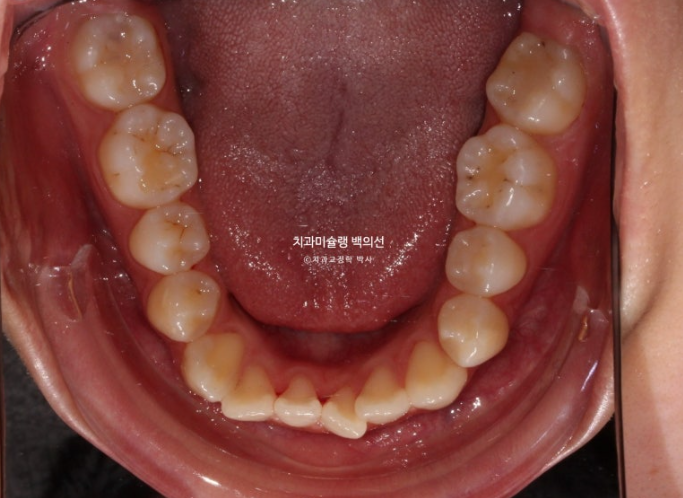

약 2년전, 교정치료를 위해 내원한 환자분입니다.

위아래 중심선이 서로 약 2mm가량 어긋나 있고 송곳니 덧니도 있습니다.

주걱턱으로 인해 앞니가 거꾸로 물립니다.

반대교합이라고 합니다.

골격성 주걱턱이라 양악수술이 필요한 상황인걸 알고 계시지만 양악수술까지는 원치 않았죠.

파란 화살표에 작은어금니가 하나 없습니다.

즉 결손치도 하나 있는 상태입니다.

만약 환자분이 작은어금니 하나가 없지 않았다면 비발치로 치료를 고려했을지도 모르나, 이미 없는 작은어금니에 균형을 맞추고자 나머지 작은어금니 3개 발치 계획을 세웠습니다.